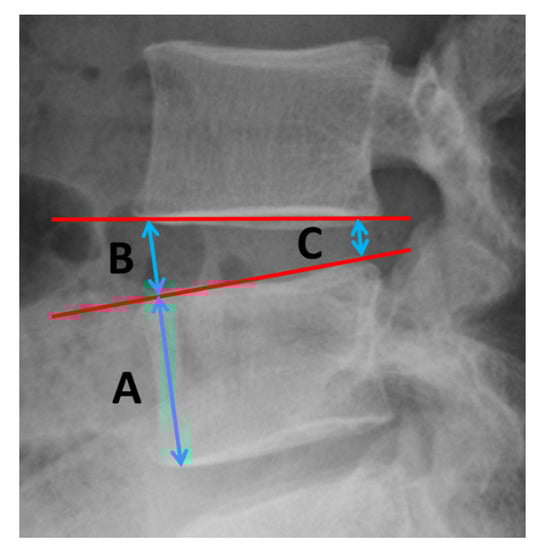

2.1. Patient Selection

2.2. Surgical Technique